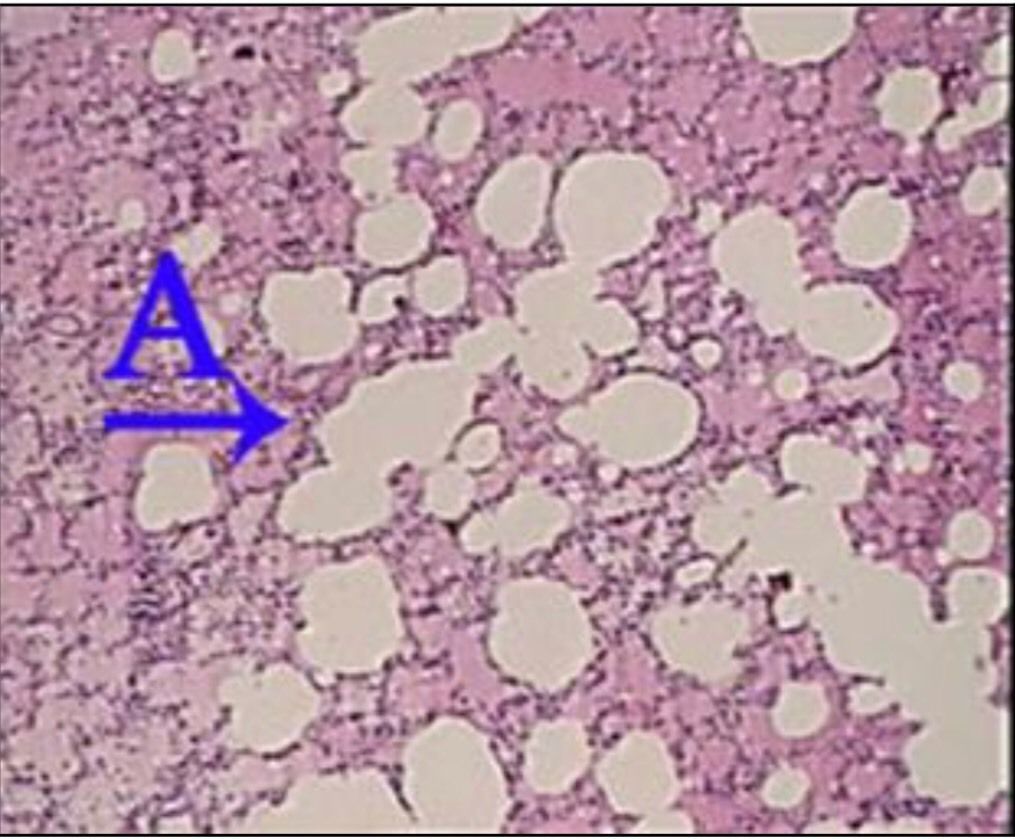

Question 56

Question

What is the correct answer at point A?

Answer

• - lésion segmentaire d’aspect homogène de pneumonie

• - exsudat œdémateux

• - la paroi alvéolaire congestive

• - alvéolite suppurée

• - des neutrophiles

Question 57

What is the correct answer at point B?

Question 58

What is the correct answer at point C?

Question 59

What is the correct answer at point D?

Question 60

What is the correct answer at point E?